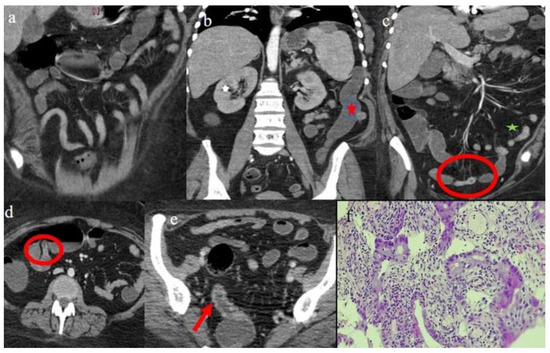

| 1 | P | P | Multisegmental and plurifocal parietal thickness with homogeneous mucosal enhancement on distal ileus | Multisegmental thickness with homogeneous mucosal enhancement | Mild diffuse comb sign and poor reactive mesenteric lymph node | Splenic infarct |

| 2 | P | P | Diffuse parietal thickness with stratified enhancement | Multisegmental thickness with homogeneous mucosal enhancement | Diffuse comb sign and poor reactive mesenteric lymph node | Mild gallbladder thickness and mild biliary tract dilatation |

| 3 | P | P | Multisegmental thickness with stratified enhancement at the terminal ileus (on CECT control at 92 days). The CECT control at 129 days showed persistence of mild parietal thickness at terminal ileus and with mucosal enhancement | Diffuse parietal thickness with stratified enhancement (On CECT control at 92 days) The CECT control at 129 days showed colic fluid distension with mild diffuse mucosal enhancement | Diffuse comb sign, mild ascites, and poor reactive mesenteric lymph node | Hepatomegaly and mild gallbladder thickness |

| 4 | P | P | Intestinal diffuse homogeneous thickness with homogeneous mucosal enhancement (on CECT control at 66 days after the HSCT); diffuse small bowel involvement with increased parietal thickness on CECT control at 120 days | Appearance of multisegmental thickness on sigma and descending colon and stratified enhancement on transverse colon on the CT FU at 120 days | Diffuse comb sign and poor reactive mesenteric lymph node | Mild gallbladder thickness and persistence of biliary tract dilatation on follow-up CT |

| 5 | P | P | Multisegmental thickness with stenosis on jejunal loops and SBO and segmental and focal thickness on the terminal ileus and appendix | Diffuse parietal thickness with stratified enhancement | Mild comb sign, poor reactive mesenteric lymph node, small air bubbles in the ascites | Small splenic areas of ischemia |